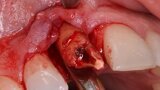

Figura 5. Hundimiento de la zona estética anterior inmediatamente después de la extracción del diente por la reabsorción de la pared vestibular.